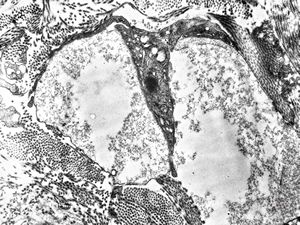

M, 28y. | leishmaniosis … skin of the cheek

M, 28y. | leishmaniosis … skin of the cheek